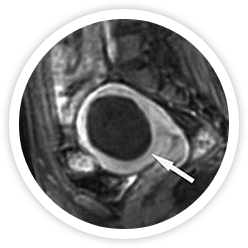

하이푸는 고강도 집속 초음파를 이용하여 입체적인 종양조직의 괴사를 유도하기 때문에 종양의 크기, 수, 모양, 위치에 따라

최적의 방법으로 종양조직의 괴사가 가능합니다. 괴사된 체내의 종양은 시간이 지나면 차차 없어집니다.

시술 전

시술 직후

시술 6개월 후

시술 1년 후